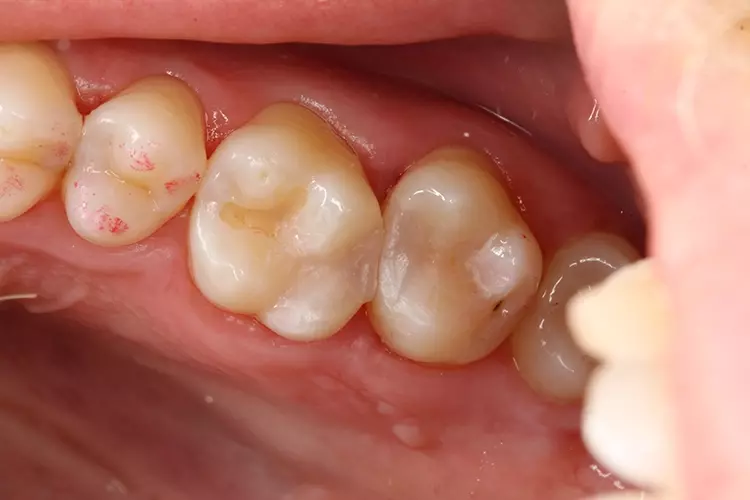

Bei einem 31-jährigen Patienten ohne Vorerkrankungen mussten aufgrund primärer und sekundärer Karies mehrere Seitenzahnfüllungen ersetzt und erneuert werden. Die Zähne 26 und 27 waren mit älteren Kompositfüllungen versorgt.

Die vorhandenen Restaurationen waren defekt und undicht, sodass sich Speisereste einlagerten (Abb. 1). Die Bissflügelaufnahme bestätigte den klinischen Befund (C2). Die Sekundärkaries hatte nur wenig das Dentin infiltriert (Abb. 2).